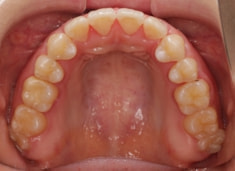

治療後(2年9ヶ月後)